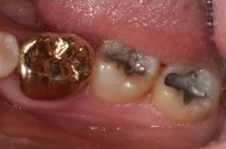

✅발치 전과 그 다음날

사랑니 발치 전과 그 다음날입니다.

절개하여 발치한 부위를 실밥으로

봉한 모습이 보입니다.

이때 2~3일 동안은

미세한 출혈이 있을 수 있으며

비릿한 피맛이 느껴질 수 있습니다.

출혈이 심하지 않는다면 이는

자연스러운 현상입니다.

발치전 / 다음날